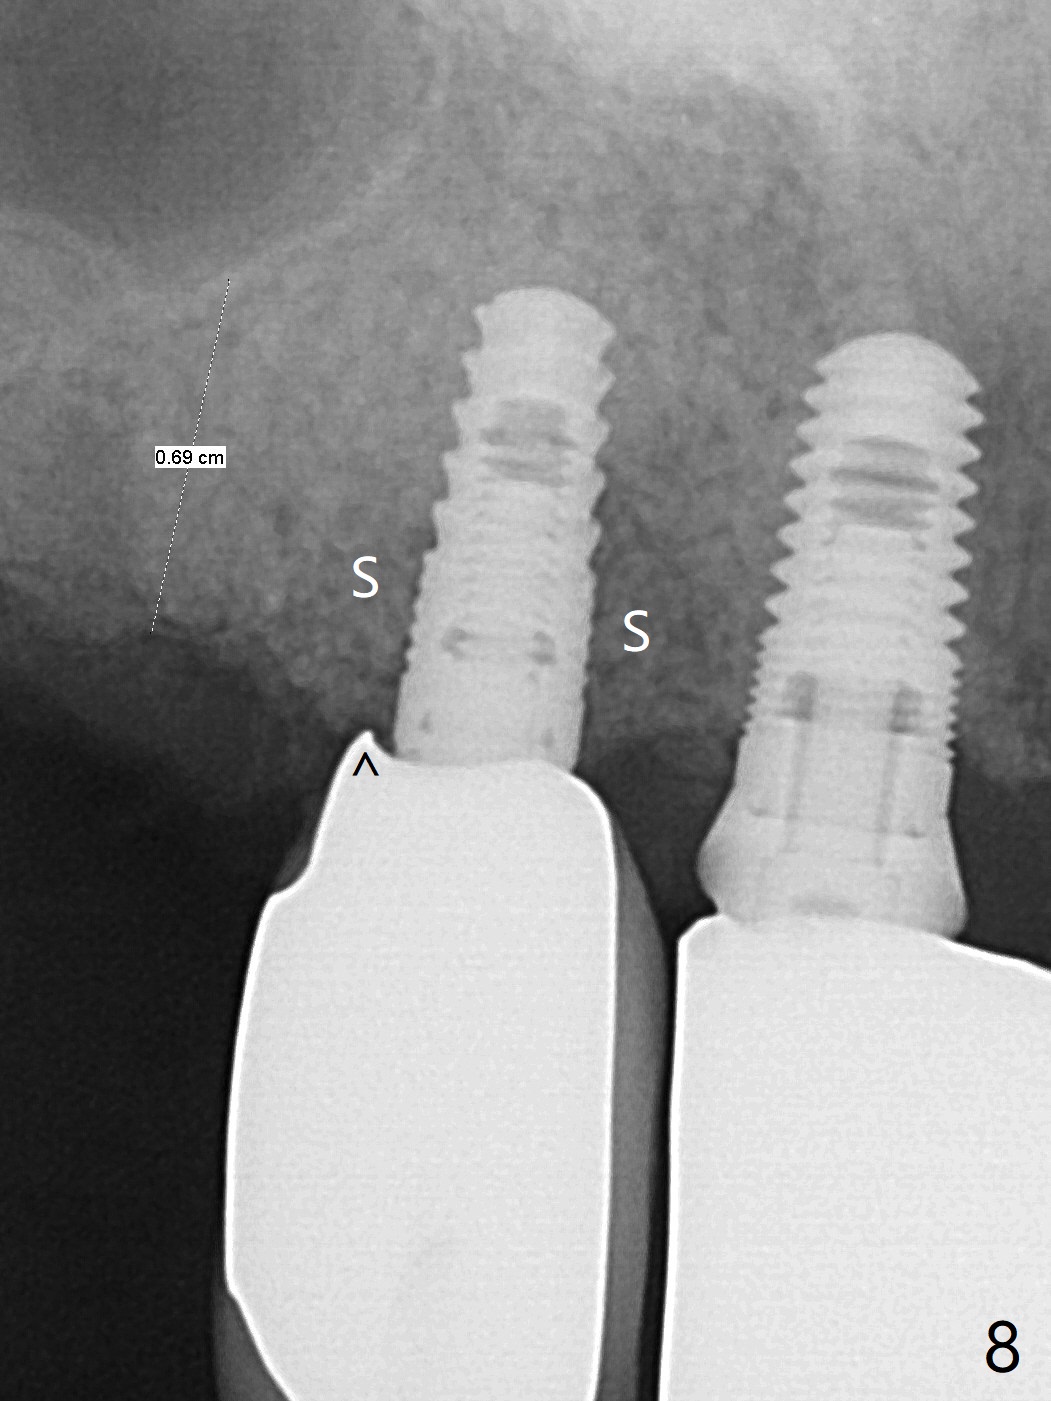

64岁女3-7牙桥,7号牙植体颊侧牙龈缘红肿(图一:*),脓液(图二:^),需要切开清洗,但是6号牙桥墩颊侧非角化龈(N)妨碍切口,所以必须去除桥墩,暴露牙槽嵴顶角化龈(图三:K),容易切开,最后缝合而不容易出血,伤口容易愈合。切开清创后重大发现是牙冠边缘(图四:^)直接接触植体微螺纹,没有基台与牙龈之间形成的屏障,有利于口腔细菌直接感染植体。直感告诉术者必须缩短牙冠边缘,抛光。然后缺损处放置粘性骨粉(图五,八:S,与图七(术前)比较),表面覆盖PRF膜,缝合(图六)。准备术后尽早去除牙冠,预防细菌再次感染。并且在6号牙位植入2x8.5毫米植体。